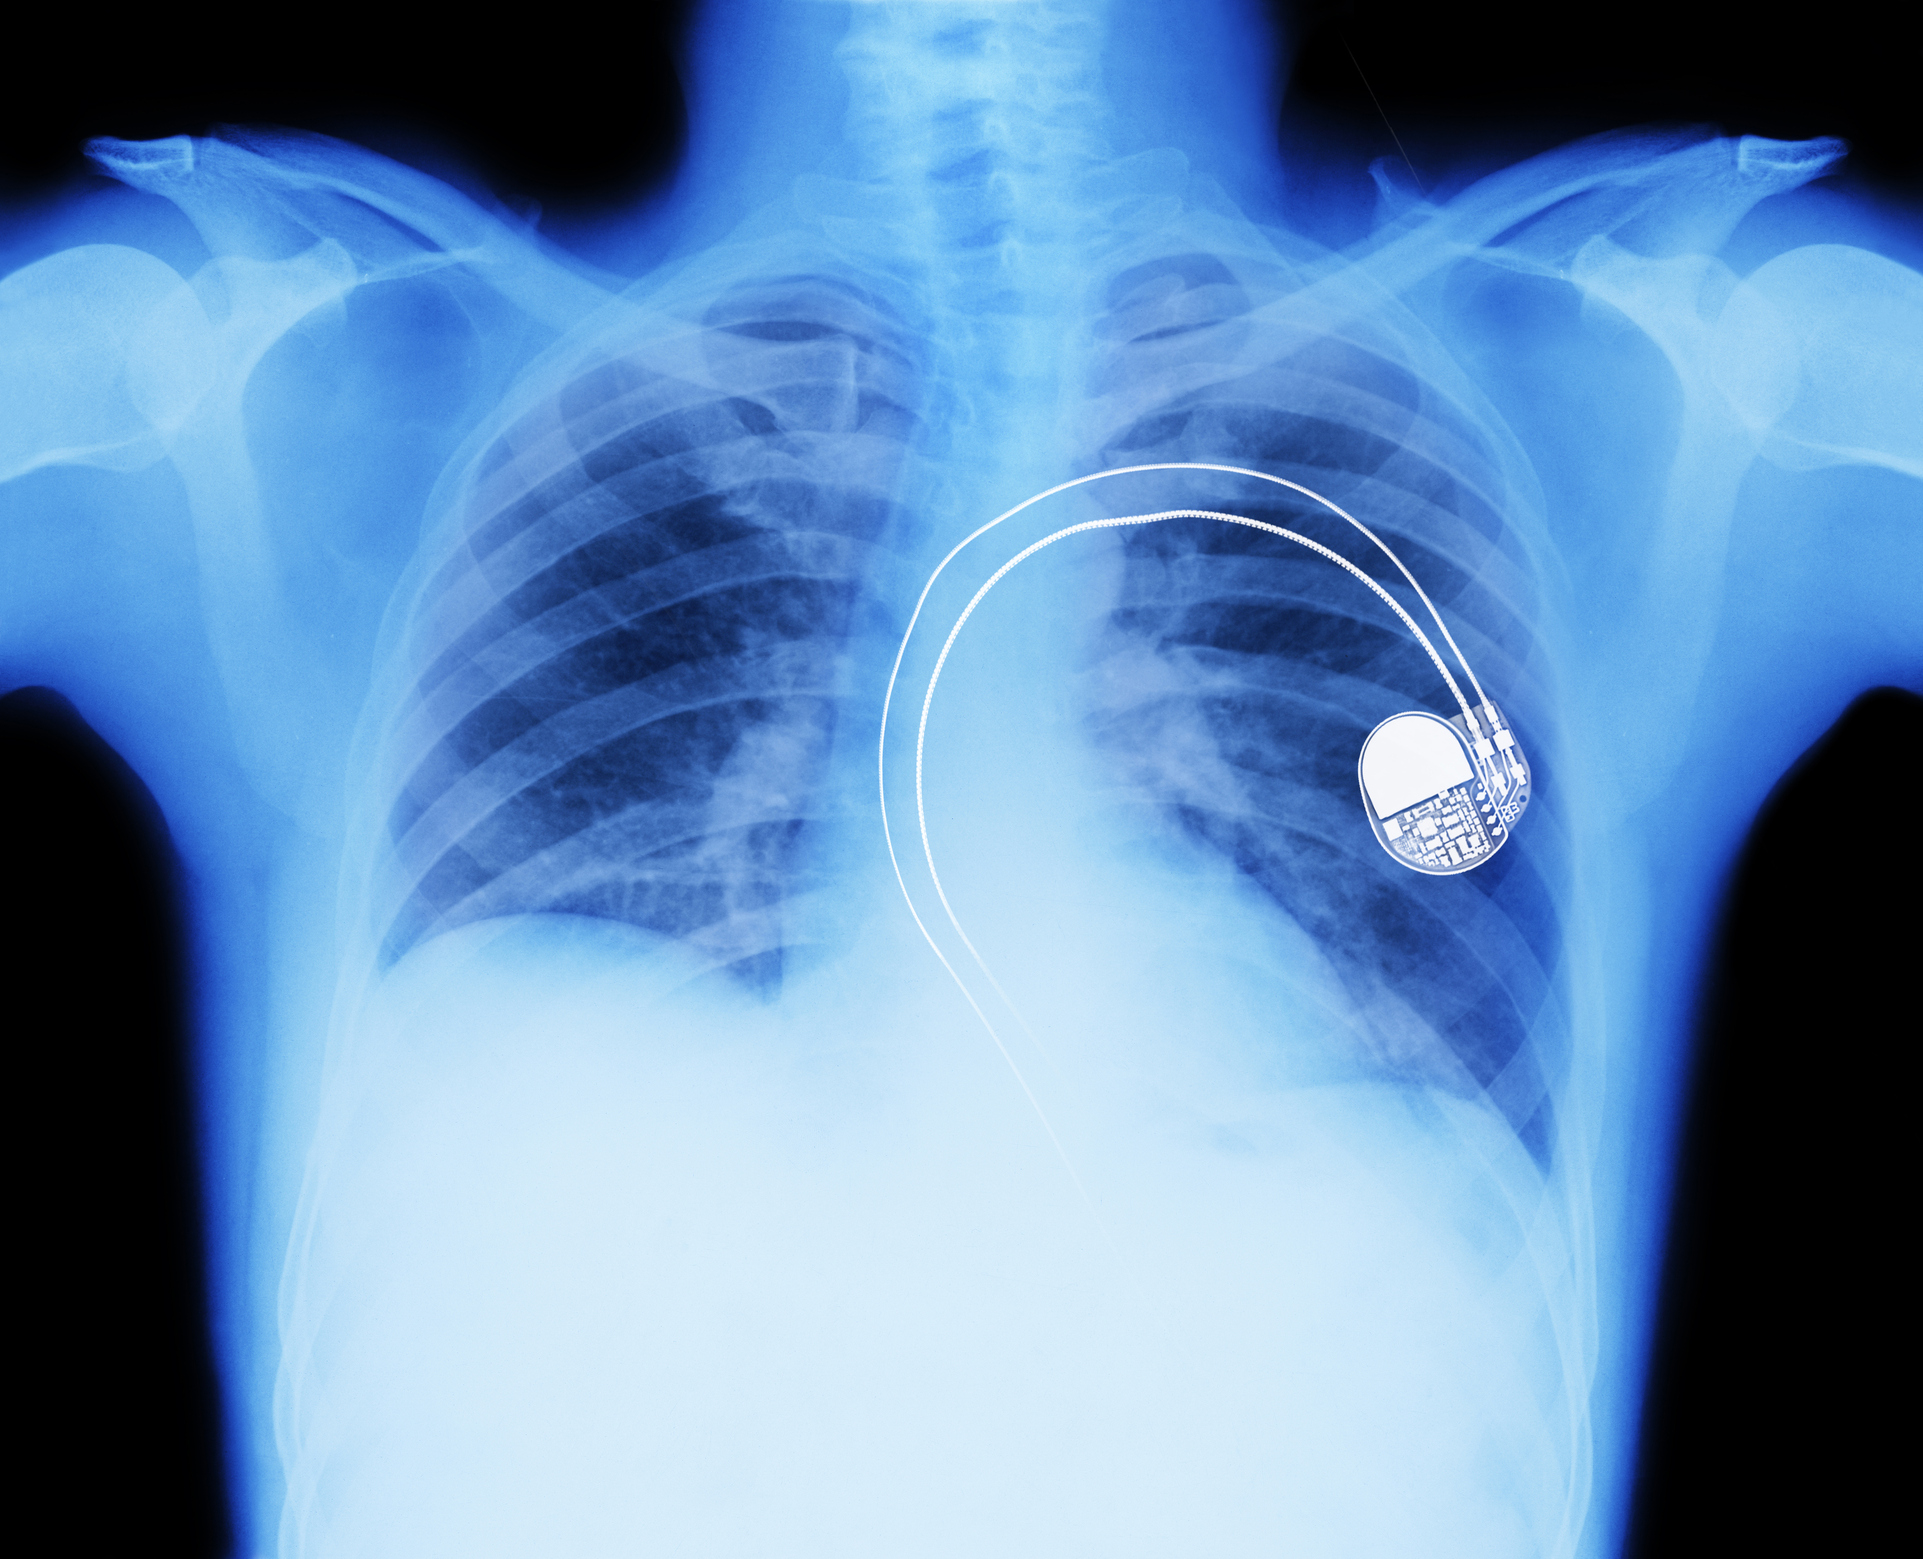

Dr. Geetha Srinivasan, the research leader at Queen’s University’s Ionic Liquid Laboratories (QUILL) research centre, explained to the BBC how the flexible supercapacitor could power medical devices, “In medical devices such as pacemakers and defibrillators there are two implants, one which is fitted in the heart and another which holds the metal based, rigid batteries—this is implanted under the skin,” Dr. Srinivasan said. “The implant under the skin is wired to the device and can cause patients discomfort as it is rubs against the skin. For this reason batteries need to be compatible to the human body and ideally we would like them to be flexible so that they can adapt to body shapes.”